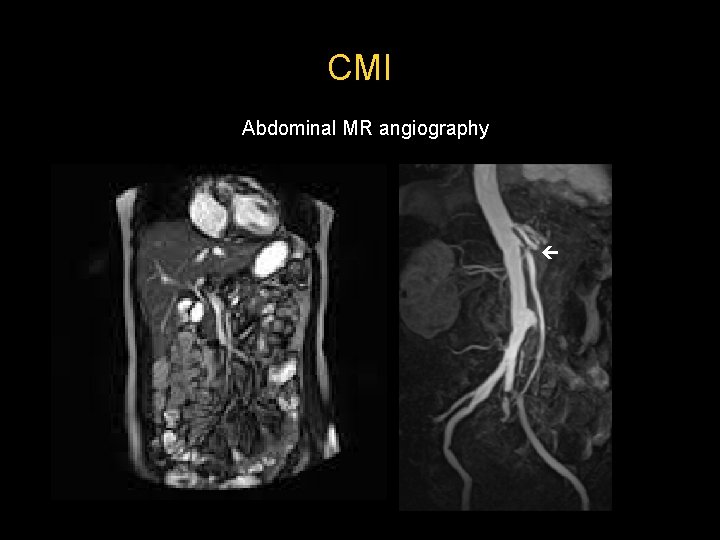

CMI Abdominal MR angiography